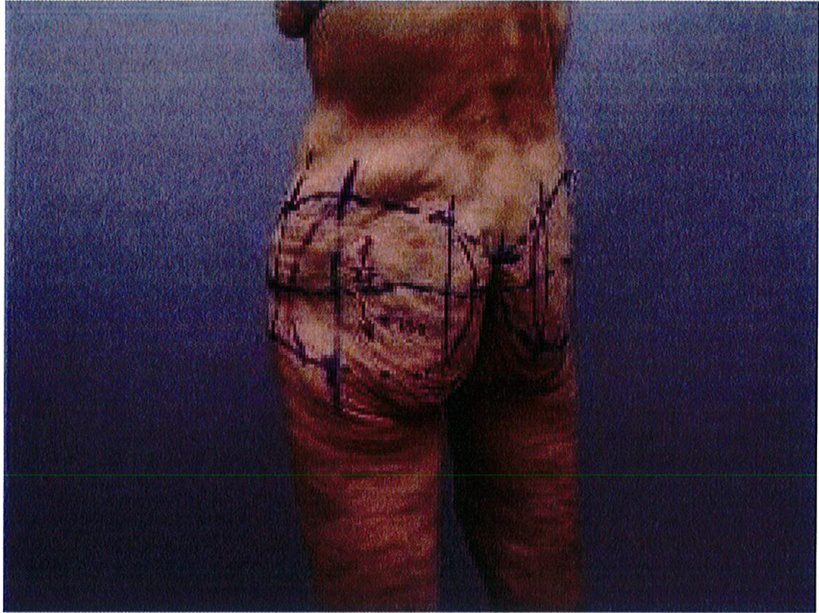

Đế giải quyết vấn đề này, chúng tôi thường yêu cầu bệnh nhân hơi nghiêng người về phía đối diện khi chúng tôi thực hiện nghiệm pháp và đánh dấu ngay lúc đó, bên đối diện cũng được thực hiện tương tự. Tiếp tục đứng ở phía sau bệnh nhân và thực hiện nghiệm pháp tương tự để đánh dấu đường rạch da ở phía mông (Hình 3). Phần mô cạnh đường giữa thường dính chặt hơn với tổ chức phía dưới, nên sẽ lấy được ít tổ chức. Sau đó, cân chỉnh lại đường vẽ phía sau và hai bên để tạo thành một chuỗi đường liên tục. Phần được đánh dấu vừa rồi là phần sẽ rạch da và sau đó khâu nối bằng các mũi purse-string. Có thể dễ dàng thấy được khi nhìn từ phía sau thì phần tổ chức cần cắt bỏ sẽ có dạng cánh bướm, đóng vai trò như môt khu vực để neo giữ

mô làm đầy bằng vật liệu tự thân để tránh chúng di lệch sang hai bên (Hình 4).

Hình. 4. Đánh dâu trước phâu thuật. Khu vực khoanh tròn màu tím chính là vùng được làm đầy bằng vật liệu tự thân bằng mô tự thân. Cần đánh dấu khi bệnh nhân đứng do da bệnh nhân rất chùng.